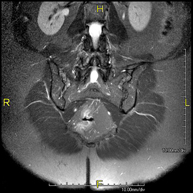

- MRI Myelography

This non-invasive diagnostic procedure uses an electromagnetic field and radio waves (from a transmitter and receiver) to acquire high-definition anatomical images of the spinal cord and nerve roots. It is a radiation-free procedure. Indicated for: hernias, spinal cord compression.